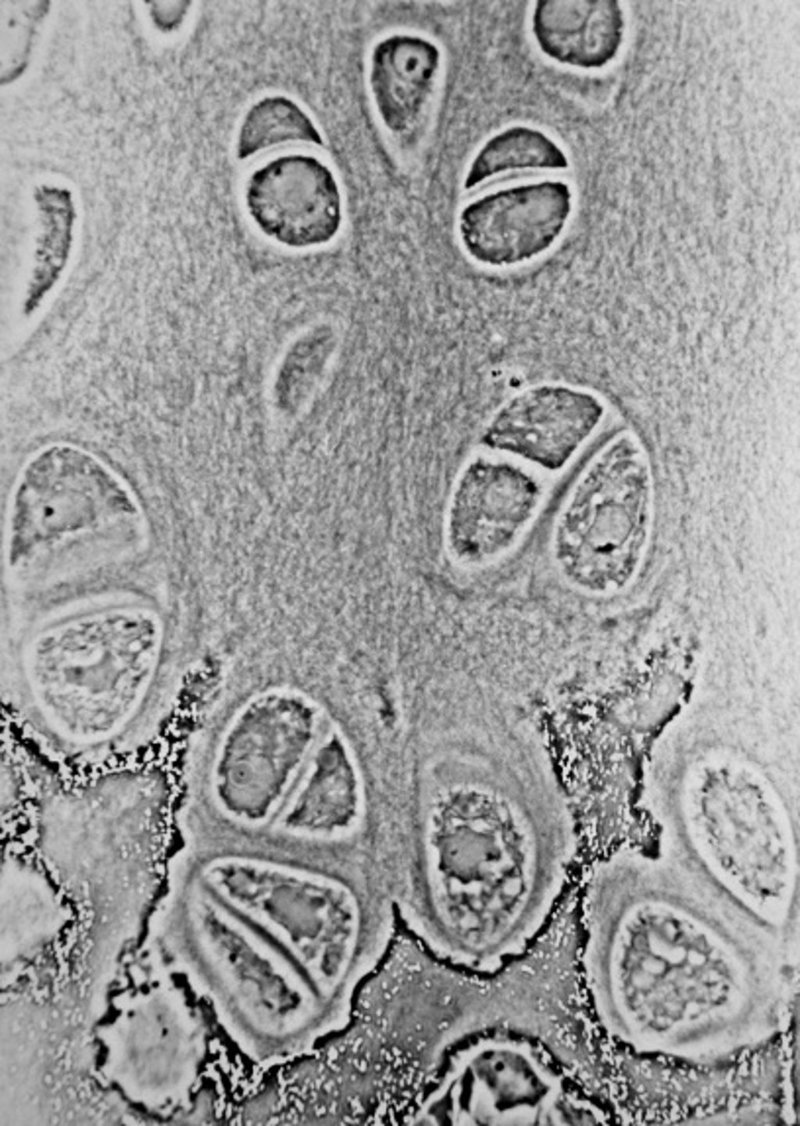

El diseño de esta impresora sigue una estructura híbrida, entre una impresora y un telar, que fabrica cartílagos sintéticos para su implantación en seres humanos. La impresora teje las fibras de un polímero recubierto con fibras biológicas y artificiales y el resultado es un cartílago artificial poroso que permitiría el desarrollo de las células humanas sobre su base para reconstruir el tejido.

Por el momento, el prototipo se ha probado en la fabricación de cartílagos para ratones y ha constituido todo un éxito. Tras ocho semanas desde su implantación, el tejido dañado de estos seres vivos se ha reconstruido a partir del cartílago artificial.